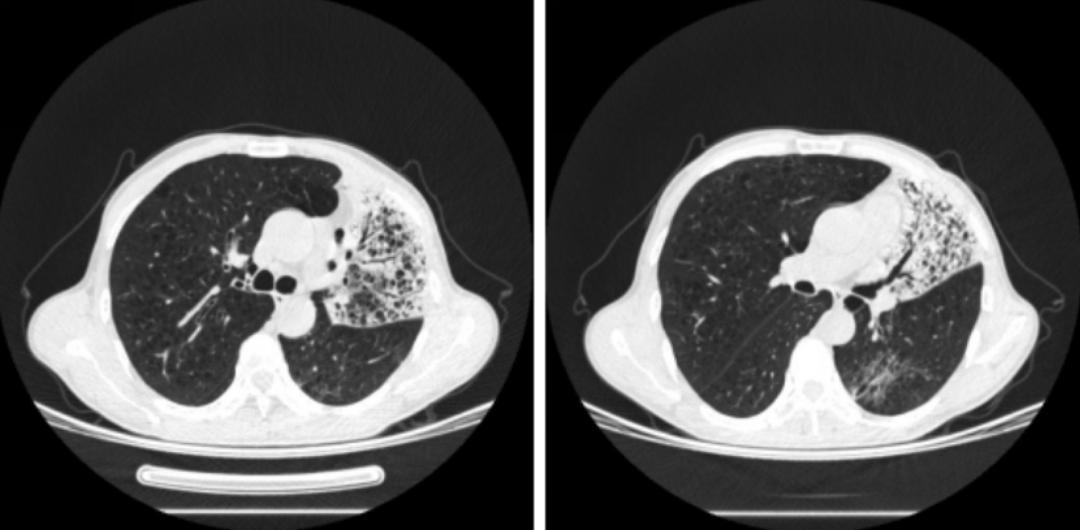

对其辅助检查的情况为:ESR 24mm/h,超敏C反应蛋白10.6mg/l,血常规、降钙素原、凝血、内毒素、真菌D-葡聚糖、半乳甘露聚糖肽、支原体、衣原体、嗜肺军团菌抗体、肝肾功、电解质、心肌酶、电解质均正常;结核感染T淋巴细胞检测阳性,结核杆菌抗体、结核杆菌DNA、PPD试验阴性;自身抗体、抗中性粒细胞抗体、风湿系列阴性;肿瘤标志物NSE 18.25 ng/ml(正常值0—16.3ng/ml);血气分析(FiO2 21.0%)示pH 457、pO2 59.9mmHg、pCO2 31.7mmHg、SaO2 92.0%。以下为该患2019年5月22日胸部CT的影像学资料:

胸部CT提示两肺可见片状密度增高影,以右肺为主,其内可见支气管充气征,两肺斑片状磨玻璃及稍高密度影,并纤细网格状影,呈铺路石改变。

入院后考虑到患者病史已达半年之久,辗转多家医院就诊,反复抗炎治疗,效果不佳,入我科后给予强效广谱抗生素美罗培加强抗感染治疗,并在治疗后复查血气分析,呼吸衰竭纠正后,于2019年5月23日行支气管镜检查,镜下可见:双侧支气管系统大量透明泡沫样分泌物溢出,右侧为著,左下叶背段支气管管口炭沫样沉积,右下叶支气管粘膜镜端触之易出血,各管腔通畅,未见肿物及狭窄,结合影像学,在右上叶前段及尖段活检。